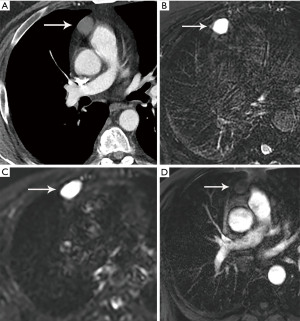

Computed tomography (CT) with contrast is the imaging modality of choice to evaluate thymic tumors due to its high spatial and temporal resolution, ease of access, and convenience. CT can reliably discern location, size/shape, morphology, margins, density, enhancement, and relationship to, or invasion of, adjacent structures (4) (Figure 2). Overall, CT is equal or superior to magnetic resonance imaging (MRI) in the evaluation of mediastinal masses with the caveat that MRI better evaluates thymic cysts or cystic components of tumors (5) (Figure 3).

MRI is not routinely utilized in thymic tumor evaluation, although, there are specific scenarios where MRI adds value, such as the differentiation of solid and cystic lesions and the evaluation of cystic or necrotic components of a mass, enhancing septations within a cyst, and the extent of local invasion (Figure 4). Chemical shift imaging can additionally be utilized to detect microscopic or intravoxel fat, which can differentiate thymic neoplasm from hyperplasia (6,7). Finally, MRI can be performed in patients who cannot receive iodinated CT or to avoid radiation exposure.

The role of fluorodeoxyglucose (FDG) positron emission tomography (PET)/computed tomography (CT) in thymic mass evaluation is incompletely defined. False-positive studies can be seen with FDG uptake in non-neoplastic masses, such as in the setting of infection, thymic hyperplasia, or fibrosing mediastinitis. False-negative studies can be seen in certain histological types of thymic malignancy with lower metabolic activity. Additionally, there is lack of technique standardization which results in quantitative variability between studies (8). Given that other prevascular masses such as malignant germ cell tumor and lymphoma are often FDG avid, the presence of a hypermetabolic prevascular mass cannot distinguish between various tumors. There are studies that report that FDG uptake can help predict tumor invasiveness and prognosis. Other studies report FDG uptake as useful in differentiating low-grade from high-grade thymic malignancies; however, other studies report these observations as controversial due to overlapping imaging findings and FDG uptake between low-grade and high-grade thymic tumors (9). Overlapping findings are less common in more aggressive tumors, such as thymic carcinoma, due to higher overall tumor metabolism, with studies reporting that a maximum standard uptake value (SUVmax) of 6 can serve as a cutoff between thymic carcinoma and lower grade thymic tumors (10) (Figures 2,3). However, this threshold cannot differentiate thymic carcinoma from other malignancies such as lymphoma or non-seminomatous germ cell tumor. Finally, PET/CT clearly has a role to detect occult metastasis in hypermetabolic tumors.